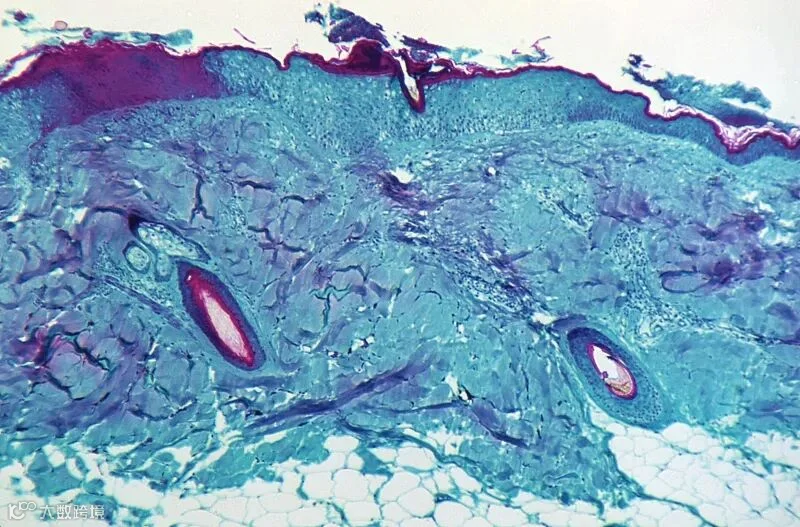

在放大50倍的情况下,显示了从一只感染了猴痘病毒的猴子皮肤病变处获取的皮肤组织切片。图源|央视新闻